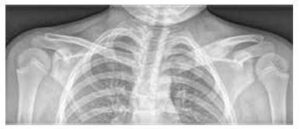

A csontok közül leggyakrabban a hosszú csontok metafízisét, a kulcscsontot, a csigolyatesteket és a medencét érinti (lásd a 2. ábrát). A csontelváltozások száma változó (néha csak egyetlen góc, gyakrabban több). Néha a csontszcintigráfia vagy a teljes test mágneses rezonancia (WB MRI) is feltárja az aszimptomatikus léziókat.

Az alapvető vizsgálat a tüneti területek natív röntgenvizsgálata (lásd a 3. ábrát), kiegészítve mágneses rezonancia és/vagy számítógépes tomográfia vizsgálattal.

A bal kulcscsont mediális végének kiterjedése és osteolitikus léziói, valamint a lágy szövetek ödémája RTG-n